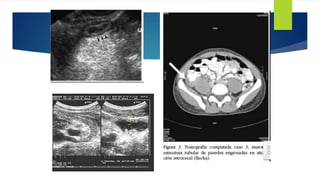

Ecografía

Sensib 95%

 Dx

 Grosor > 6mm

 Distención luminal

 Masa en FID Fecalito

 Engrosamiento asimétrico

 Liquido libre intraperitoneal

 Edema tejido circundante

TAC  Apéndice de paredes gruesas distendidas

 Estriación inflamatoria de la grasa circundante o flemón o absceso pericecal.

 Los apendicolitos se muestras mas fácilmente con tac que con radiografías simples.

Ecografía Sensib 95%  Dx Grosor > 6mm  Distención luminal  Masa en FID Fecalito  Engrosamiento asimétrico  Liquido libre intraperitoneal  Edema tejido circundante

TAC  Apéndicede paredes gruesas distendidas  Estriación inflamatoria de la grasa circundante o flemón o absceso pericecal.  Los apendicolitos se muestras mas fácilmente con tac que con radiografías simples.